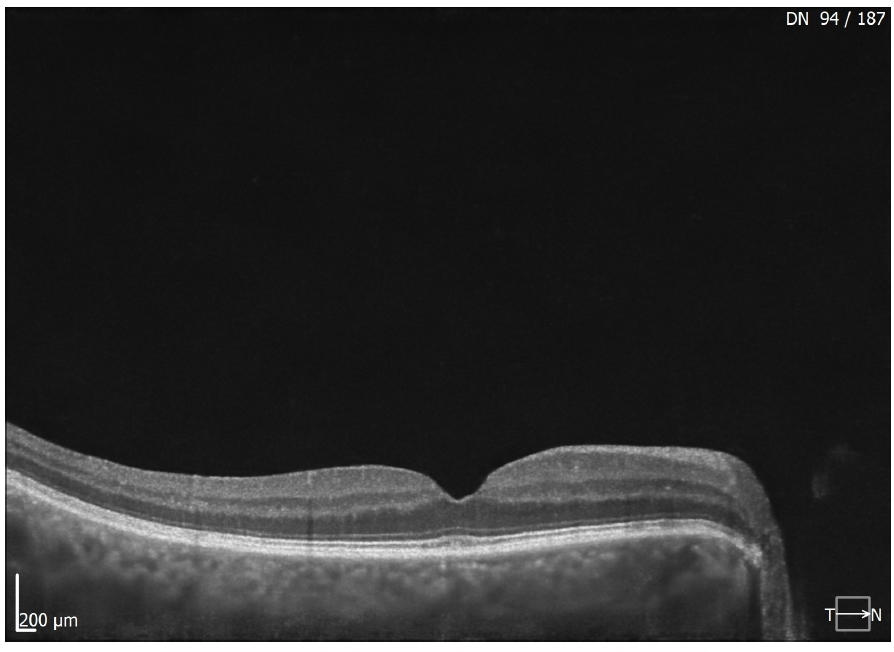

SDOCT e Angio-OCT